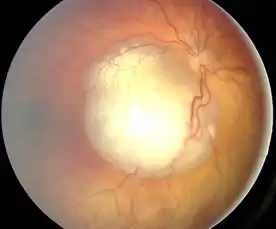

An ocular ultrasound of a large retinoblastoma tumor within the eye of a 3-year-old boy Funduscopic finding of a retinoblastoma

Funduscopic finding of a retinoblastoma Ocular fundus aspect of retinoblastoma

Ocular fundus aspect of retinoblastoma Large exophytic white tumor with foci of calcification producing total exudative retinal detachment

Large exophytic white tumor with foci of calcification producing total exudative retinal detachment Flexner-Wintersteiner rosettes in retinoblastoma